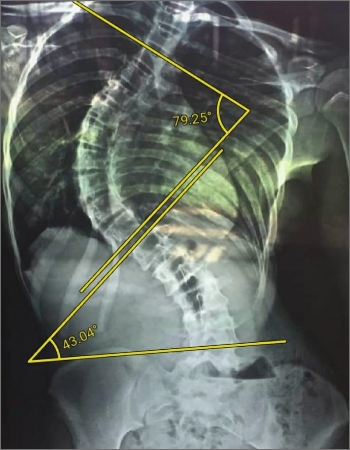

A shy young girl asima (name changed for privacy) from a picturesque small town in the northern part of Sri Lanka was noticing some changes to her spine. She had begun to notice a curve in her back. Such a condition is called scoliosis. Though it is three dimensional deformity, a plain x-ray would show the spine that looks like an “S” or a “?”. She was diagnosed to have a severe case of idiopathic (no known cause) kypho scoliosis. While most cases in children are congenital (something we are born with), Scoliosis may occur due to the result of disease or injury however 70 – 80 % of cases are classified as idiopathic; that is there is no known cause. All these changes in our body are possible because of muscles weakness and imbalance. Weak, overloaded, stretched or shortened muscles lose their supportive function. These muscle imbalances cause further problems like uneven weight distribution and enforce the “scoliotic balance” of the body. This may lead to, back and leg pain due to pressure on the spinal cord and nerves, degenerative changes in the spine, vertebrae and discs becoming compressed and wedged on one side. This can get worse with increasing age as the skeleton gets matured, as it may lead to “Frozen chest”, a condition of limited chest expansion, which can lead (in severe cases) to decreased breathing capacity. Overall these patients have limited or restricted spine motion. Scoliosis often presents itself, or worsens, during the adolescence growth spurt and is more often diagnosed in females than males. That was happening to poor asima as she was noticing something was wrong with her, and she could not run or play like she used to before. She could hardly catch a deep breath and she was worried.

When she arrived in Sooriya Hospital Chennai, the doctors evaluated her and diagnosed her to be ailing from adolescent idiopathic scoliosis (Lenke’s type 1B). Dr.Sudhir, our spine surgeon proposed corrective surgery with multilevel implants and cantilever bending to correct the flexion (bending) deformity. This was done under the most advanced continuous neuromonitoring, to ensure there is no damage to the vital spinal cord. The operation was a great success, stated Dr. C.P Sreekumar our M.D, who himself is a orthosurgeon. The deformity was corrected as planned with minimal to no collateral damage. After the surgery asima is recovering well. She likes to play in the garden and wants to study more. She was beaming with a bright smile when asked how she felt and replied “I can breathe easily now”. She is under continuous monitoring and care, but her outcome is heartwarming and now we are sure she can stand tall and walk proud.